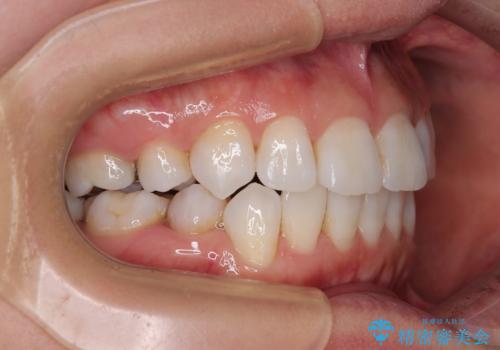

矯正治療の後戻り インビザラインで短期間矯正治療

- 上下前歯の後戻りを気にして来院された患者様です。

インビザラインでの治療を希望されていて、デコボコの程度が中等度であり、安価なパッケージにて対応可能と判断されたため、インビザライン・モデレートを用いて矯正治療を行うこととしました。